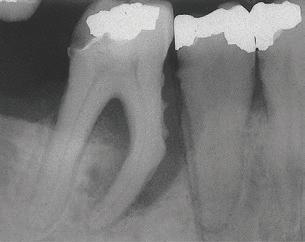

Stage IV –Severe Periodontitis

The American Academy of Periodontology (AAP) released a comprehensive update for the classification and documentation of periodontal and peri-implant diseases and conditions. This comprehensive update was developed and implemented because of the overwhelming information confirming the link between oral health and whole-body health. The first update the dental profession has seen since 1999, the updated classifications include a framework for staging and grading as well as defining the distribution of disease.

The staging consists of the severity of the disease and the complexity for disease management, while the grading defines the rate of progression, a patient’s overall health, social habits, and the expectation of how well the disease will respond to treatment. Distribution expresses if the disease is localized or generalized.

This new classification and documentation of periodontal disease takes into consideration a patient’s current oral condition, health history, and risk factors. This information helps assess how serious an infection in the gingival tissue and underlying bone can be for a patient’s oral health and whole-body health.

THE AMERICAN ACADEMY OF PERIODONTOLOGY UPDATES DISEASE CLASSIFICATIONS

Recognizing and treating periodontal disease in its earliest stages results in better patient outcomes and has been shown to positively affect the long term whole-body health of patients. Early disease recognition and management can only be accomplished by performing a thorough comprehensive exam which includes, but is not limited to, an oral cancer exam, full mouth pocket charting, and radiographs with a clear view of the interdental crestal bone. As clinicians, we know radiographic bone loss, no matter how minor, is a result of a long-standing infection in periodontal tissue.